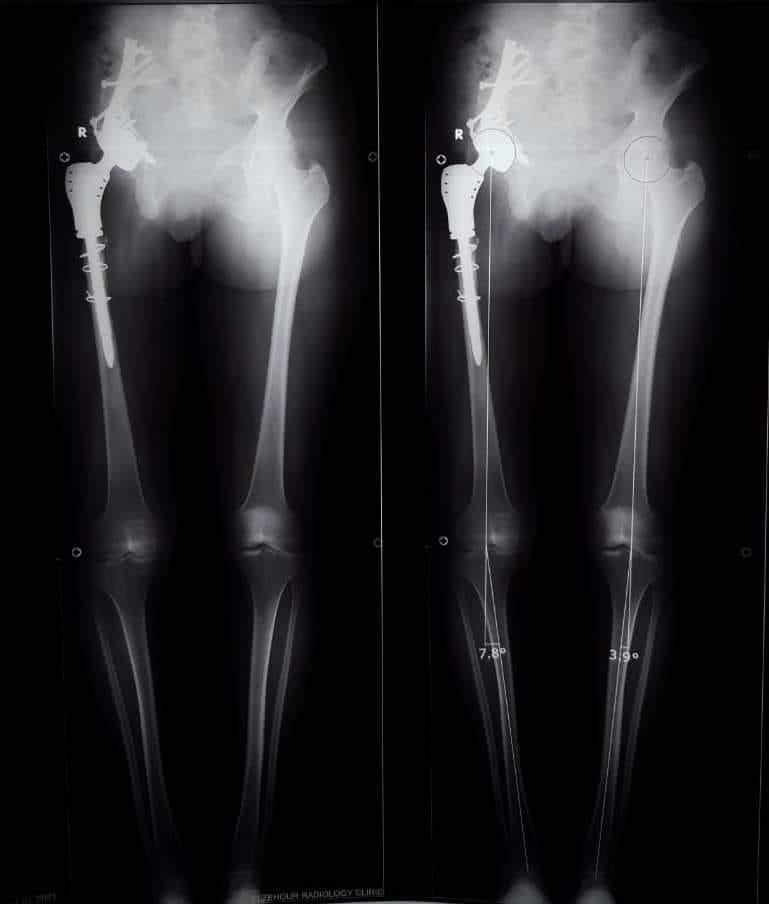

وأوضح الدكتور عمرو السيد علي أستاذ جراحة العظام ، واستشاري الجراحات الميكروسكوبية بجامعة أسيوط ، أن المريضة تبلغ من العمر 15 عامًا ، وكانت تعاني من وجود ورم في عظمة الآلية، ومفصل الحوض؛ مشيرًا إلى إجراء العملية الجراحية على مرحلتين في إطار زمني 3 شهور ؛ لتجنب البتر؛ حيث تم في المرحلة الأولي إزالة الورم من عظمة الآلية، ونقل الجزء العلوي من عظمة الفخذ ؛ لتحل محل عظمة الآلية.

وأوضح الدكتور محمد مهران أستاذ جراحة العظام المساعد، واستشاري جراحات تغيير المفاصل الصناعية بجامعة أسيوط، أنه تم- بعد إجراء الفحوصات الطبية- تركيب مفصل صناعي كامل ذي مواصفات خاصة للحوض، وذلك دون اللجوء لتثبيت المفصل، ولتجنب البتر لهذا الطرف؛ مشيرًا إلى نجاح العملية، واستقرار الحالة الصحية للمريضة، وتمت متابعتها؛ لحين عودة حركة المريضة لصورتها الطبيعية، ومشيرا في الوقت نفسه، أنه تم نشر العملية الجراحية عالميًا: في مجلة علمية متخصصة للحالات الصعبة؛ بمساعدة الدكتور أحمد عادل خليفة مدرس جراحة العظام بكلية طب قنا- جامعة جنوب الوادي.